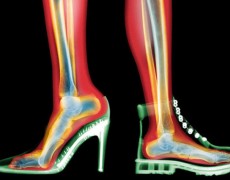

Τι δείχνει η εξέταση του πελματογραφήματος; »

ΠΕΛΜΑΤΟΓΡΑΦΗΜΑ »